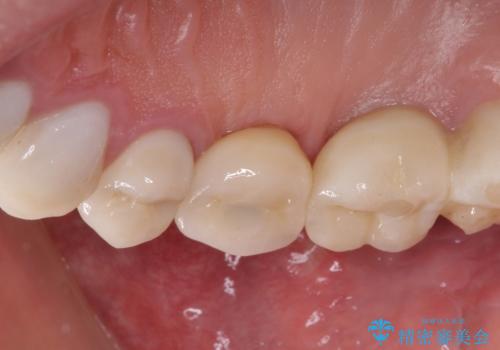

折れてしまった歯 インプラントによる補綴治療

- 咬合力により歯が割れてしまった方のインプラント治療です。